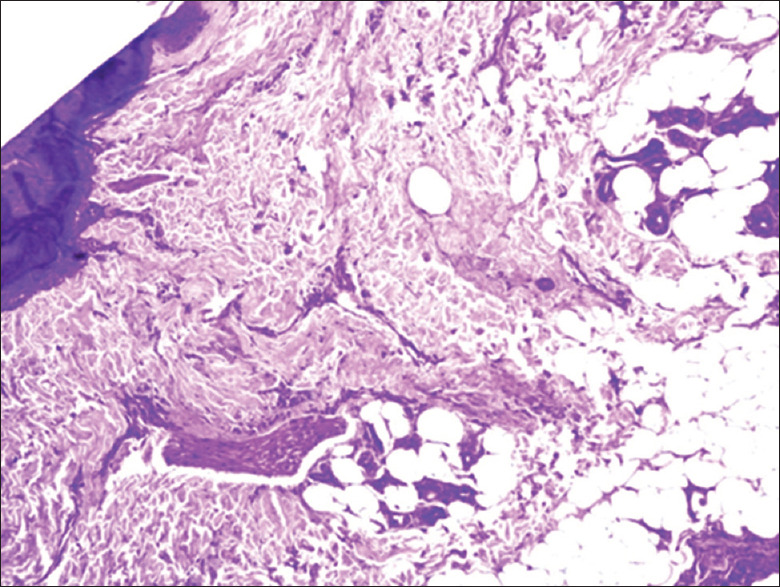

Materials and methods: This cross-sectional study was conducted over a period of 1 year in the department of dermatology and pathology in a tertiary care hospital in North India. Adult patients (age >18 years) presenting with patchy cicatricial alopecia as well as clinically doubtful noncicatricial conditions over the scalp were included in this study. In doubtful cases of noncicatricial alopecia, a single 4-mm punch biopsy was performed for transverse sectioning with hematoxylin and eosin stain. In all cases of cicatricial alopecia, two 4-mm punch biopsies were performed, one for transverse sectioning and the second for vertical sectioning and direct immunofluorescence (DIF). The final diagnosis was made on the basis of the trichopathologic findings.

Results: A total of 23 cases were included in our study with the majority (52.2%) being in the age group of 20-30 years. The mean age at diagnosis was 30.5 ± 11.38 years. On the basis of trichopathologic findings, a final diagnosis was made in 18 (78.3%) cases. However, 5 (21.7%) cases remained undiagnosed and were labeled as nonspecific. According to the final diagnosis based on the trichopathologic findings, maximum cases were of discoid lupus erythematosus (DLE) (26.1%), followed by lichen planopilaris (21.7%), pseudopelade of Brocq (13%), alopecia areata (8.7%), folliculitis decalvans (4.3%), and traction alopecia (4.3%). Trichopathologic examination revealed hyperkeratosis (60%), basal cell vacuolization (55%), epidermal atrophy (55%,) perifollicular lymphocytic infiltrate (30%), pigment incontinence (30%), perifollicular fibrosis (25%), and thickened basement membrane (25%). Only four cases showed deposits of immunoreactants in DIF and all four were finally diagnosed as DLE.